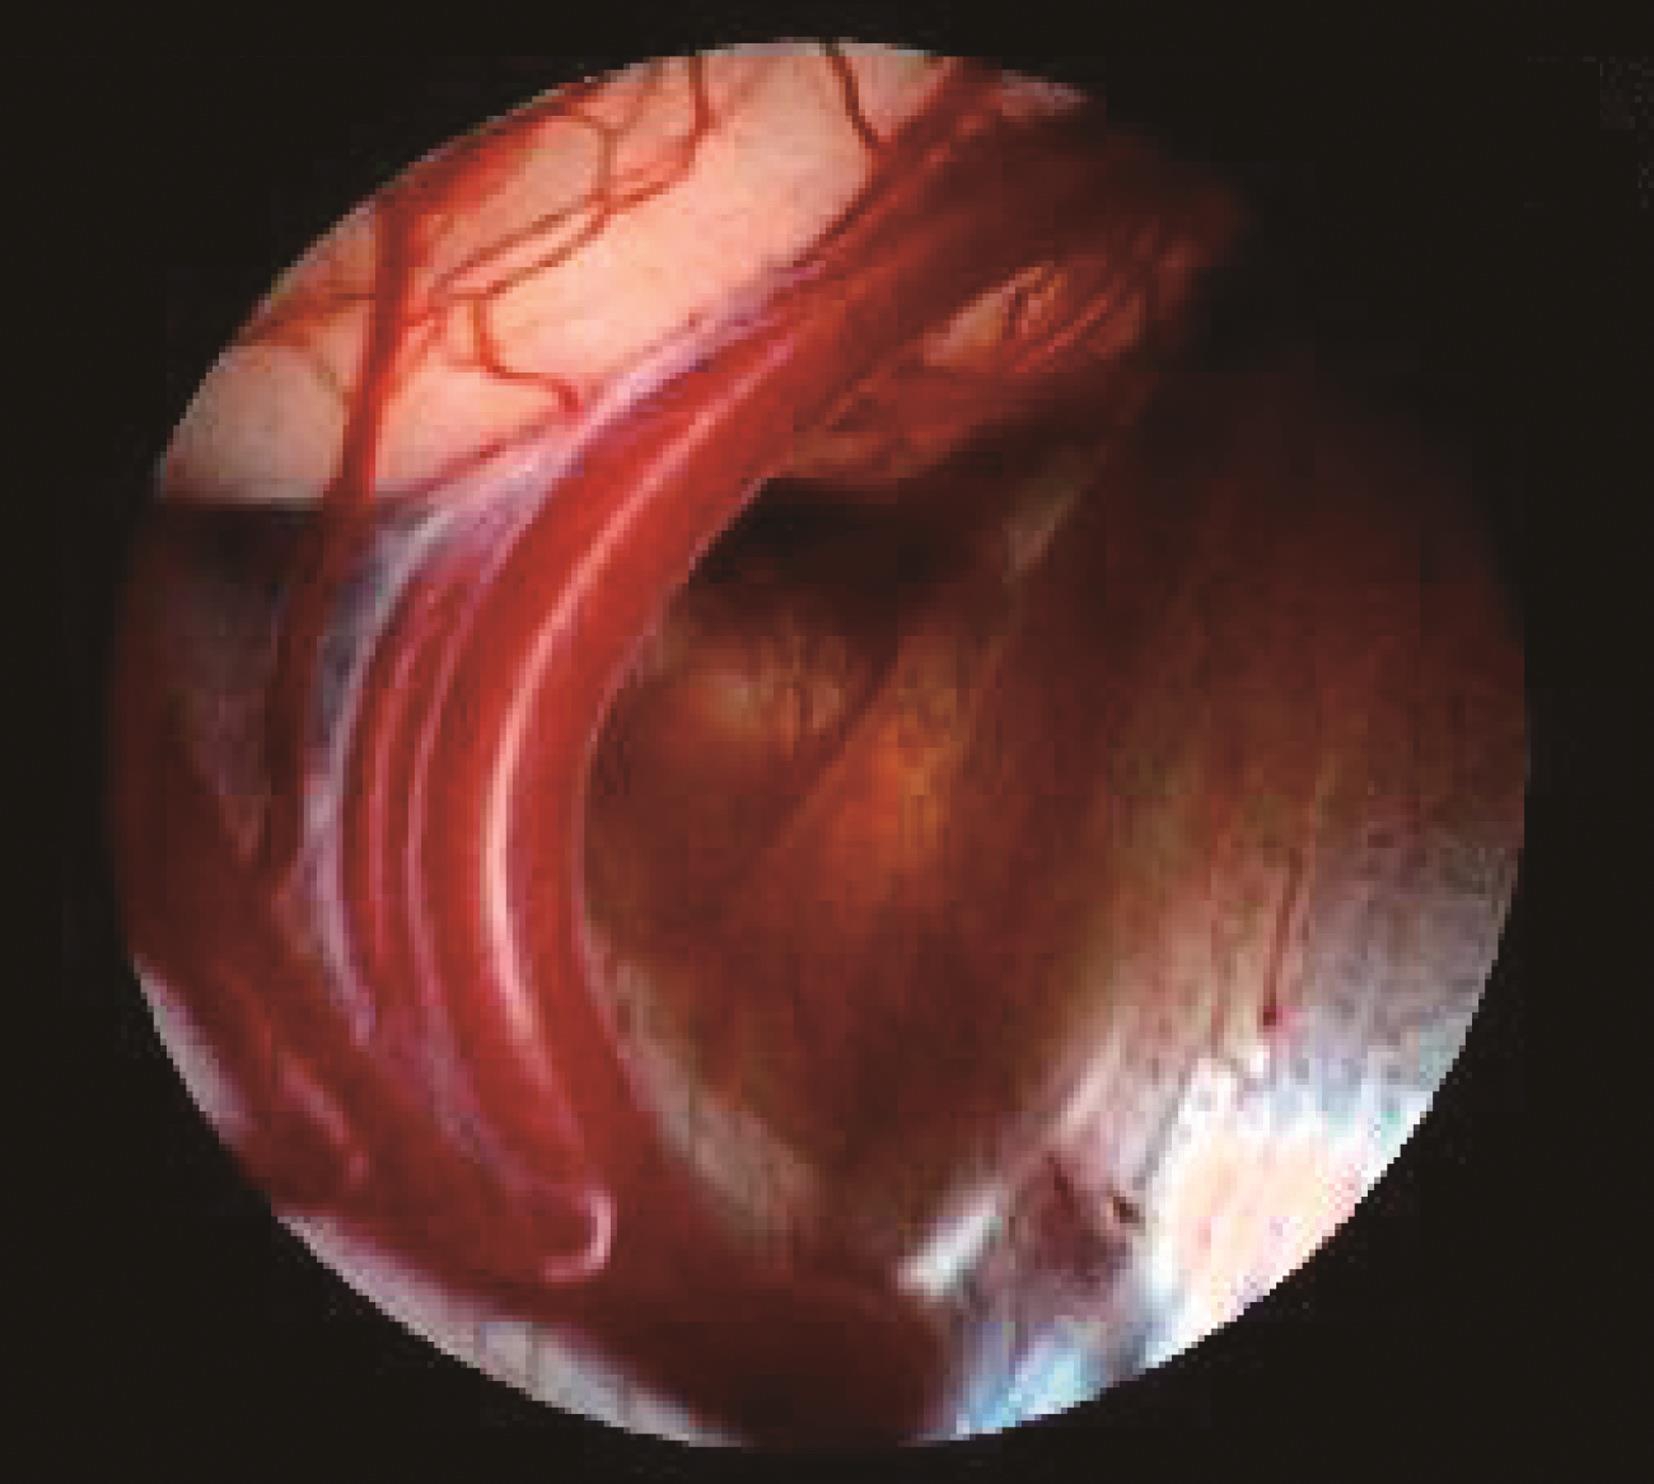

图3-1-1-3 内镜下脑室探查,明确导

a.头颅磁共振矢状位片提示导水管梗阻;b.内镜下探查证实导水管内肿瘤